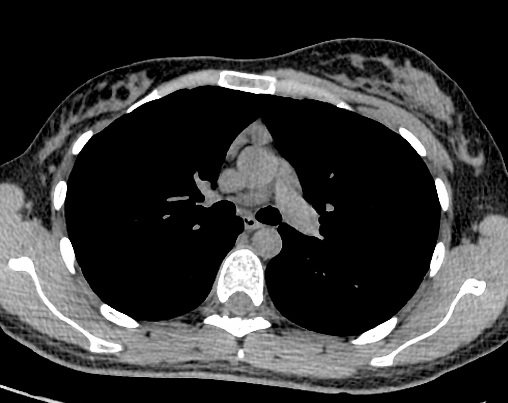

Image radiologique TDM en

coupe axial de aplasia du muscle pectoralis majeur

gauche d'une syndrome de Poland |

Même cas en coupe axiale TDM

fenêtre mediastinale . |